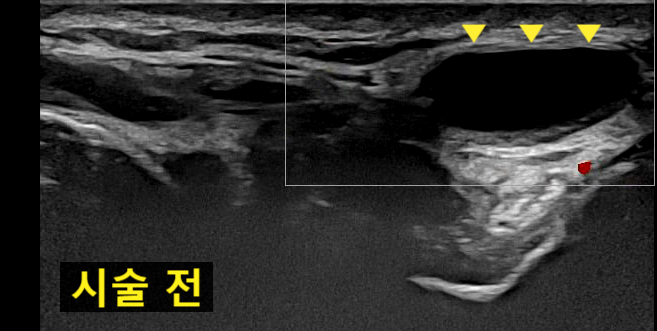

시술 전 / 24년 5월 21일

맨 눈으로 봐도

아주 큰 물혹이였지만

초음파상

거대한 결절종이 보입니다.